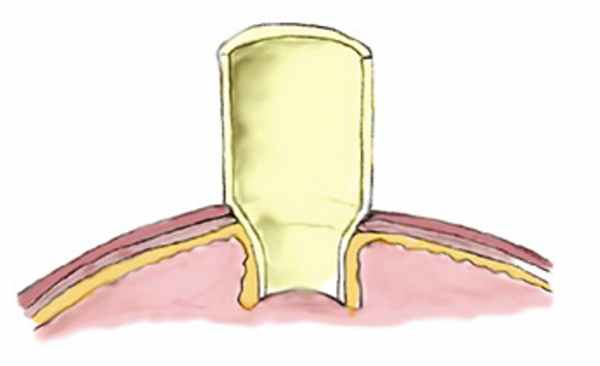

На следующем этапе сформирован антирефлюксный мочеточниково-пузырный анастомоз. Для этого на противобрыжеечном крае кишки отсепаровали и удалили ее серозно-мышечный слой на участке размером 5×20 мм. Мочеточник уложили до середины выкроенной площадки. На заднюю полуокружность мочеточника и верхний край рассеченной серозно-мышечной оболочки наложили узловые швы. После сшивания задней губы анастомоза в мочеточники установили интубатор (мочеточниковый катетер) и сшили переднюю губу анастомоза. Далее наложили прошивные лигатуры на верхний и нижний края серозно-мышечной площадки. При подтягивании за нити и погружении оболочек диссектором произвели инвагинацию мочеточника в просвет тонкой кишки (рис. 4, на цв.вклейке). По углам анастомоза остаются неушитыми участки тонкой кишки длиной 1 см. На серозно-мышечные оболочки кишки как правого, так и левого угла необходимо наложить 2—3 узловых шва. После этого мочеточниковые интубаторы следует вывести через дистальный отдел мочевого пузыря (рис. 5, на цв. вклейке).

Рис. 4. Окончательный вид уретеронеоанастомоза (схема).